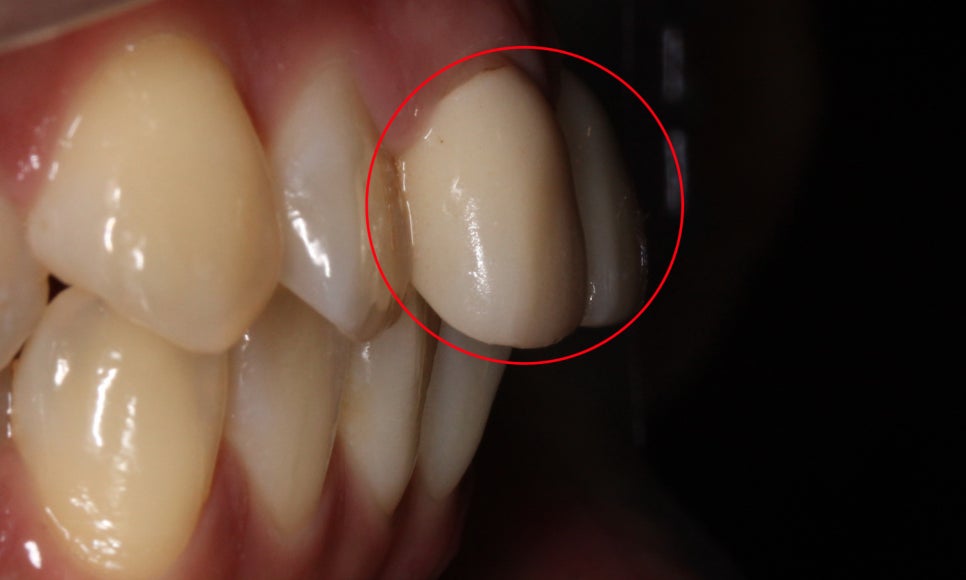

전치부의 측면 사진을 보시면

중절치의 토끼앞니 증상을

더 명확하게 확인할 수 있는데요,

특히 중절치와 잇몸 사이의 경계가

PFM크라운 치료 후 패여있는 느낌이 있어

크라운 보철의 재수복이 필요한 모습입니다.